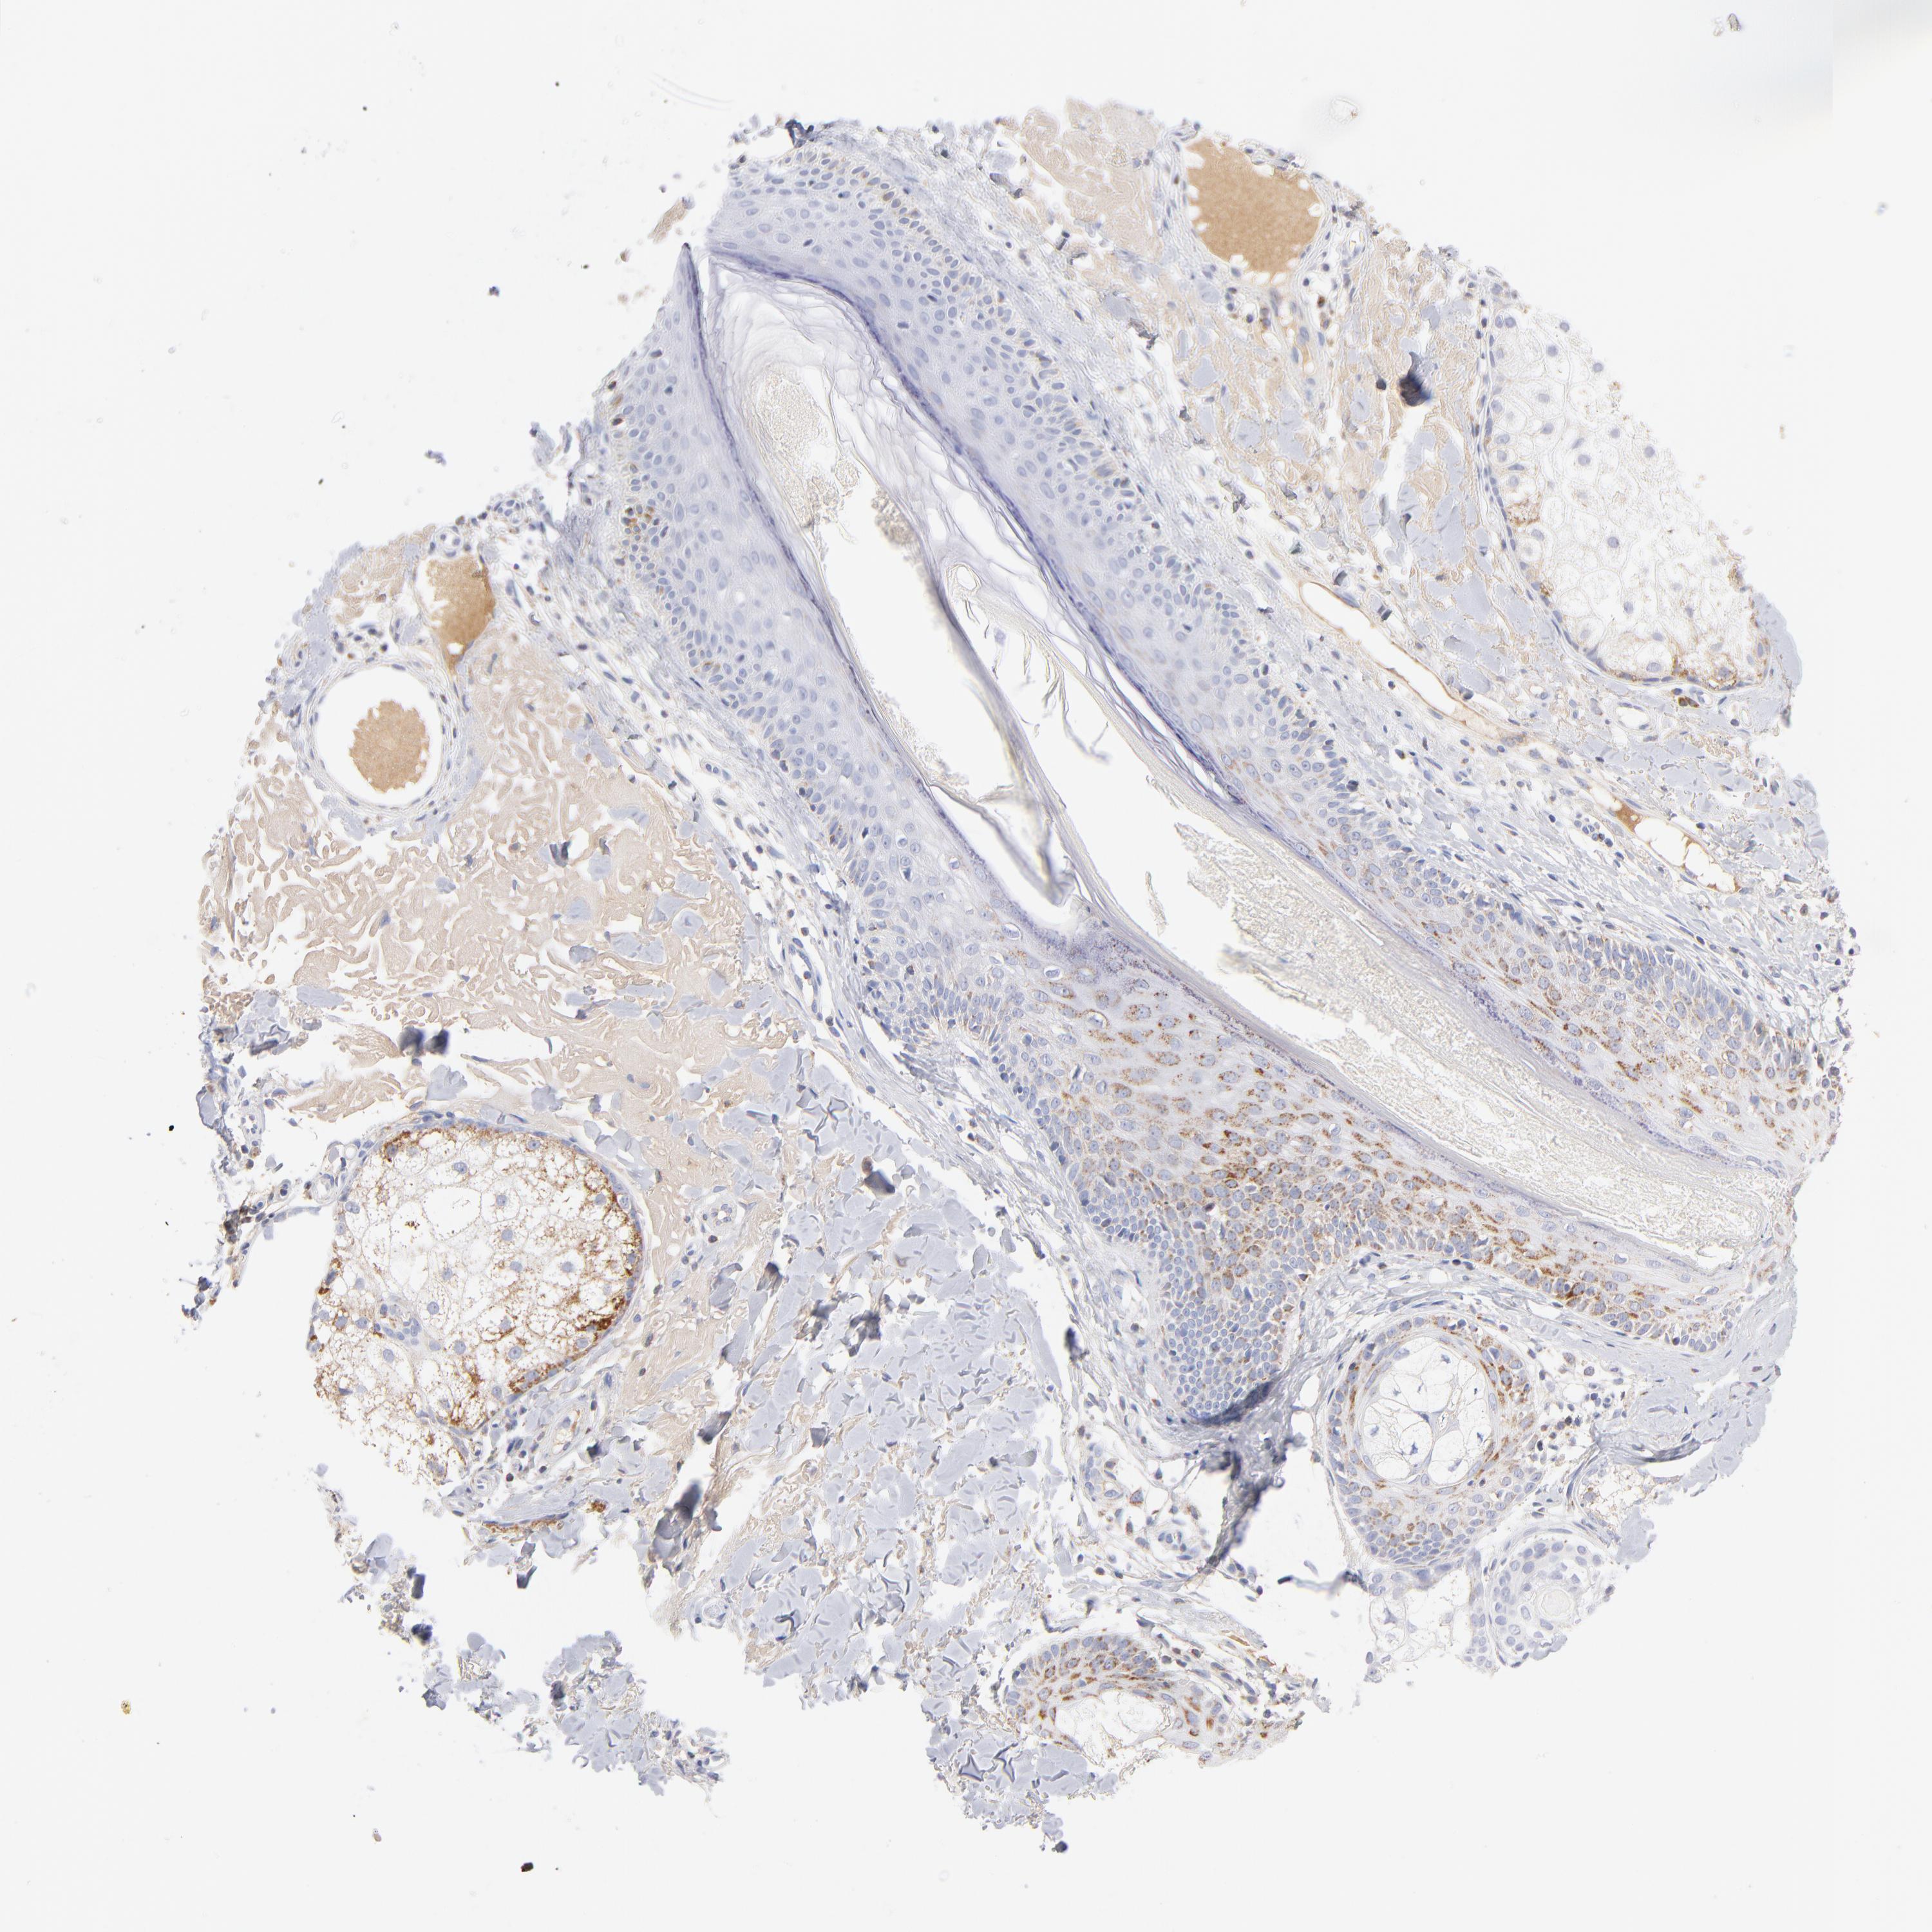

Basal cell and squamous cell cancer

SKIN CANCER - Protein expressioni

A mouse-over function shows sample information and annotation data. Click on an image to view it in a full screen mode. Samples can be filtered based on level of antibody staining by selecting one or several of the following categories: high, medium, low and not detected. The assay and annotation is described here.

Antibody stainingi

Antibody staining in the annotated cell types in the current human tissue is reported as not detected, low, medium, or high, based on conventional immunohistochemistry profiling in selected tissues. This score is based on the combination of the staining intensity and fraction of stained cells.

Each image is clickable and will lead to virtual microscopy that enables deeper exploration of all samples and also displays staining intensity scores, fraction scores and subcellular localization as well as patient and tissue information for each sample.

Antibody HPA040786

Antibody CAB003782

Staining

High

Medium

Low

Not detected

Intensity

Strong

Moderate

Weak

Negative

Quantity

>75%

75%-25%

<25%

None

Location

Nuclear

Cytoplasmic/membranous

Cytoplasmic/membranous,nuclear

Squamous cell carcinoma, NOS

Basal cell carcinoma